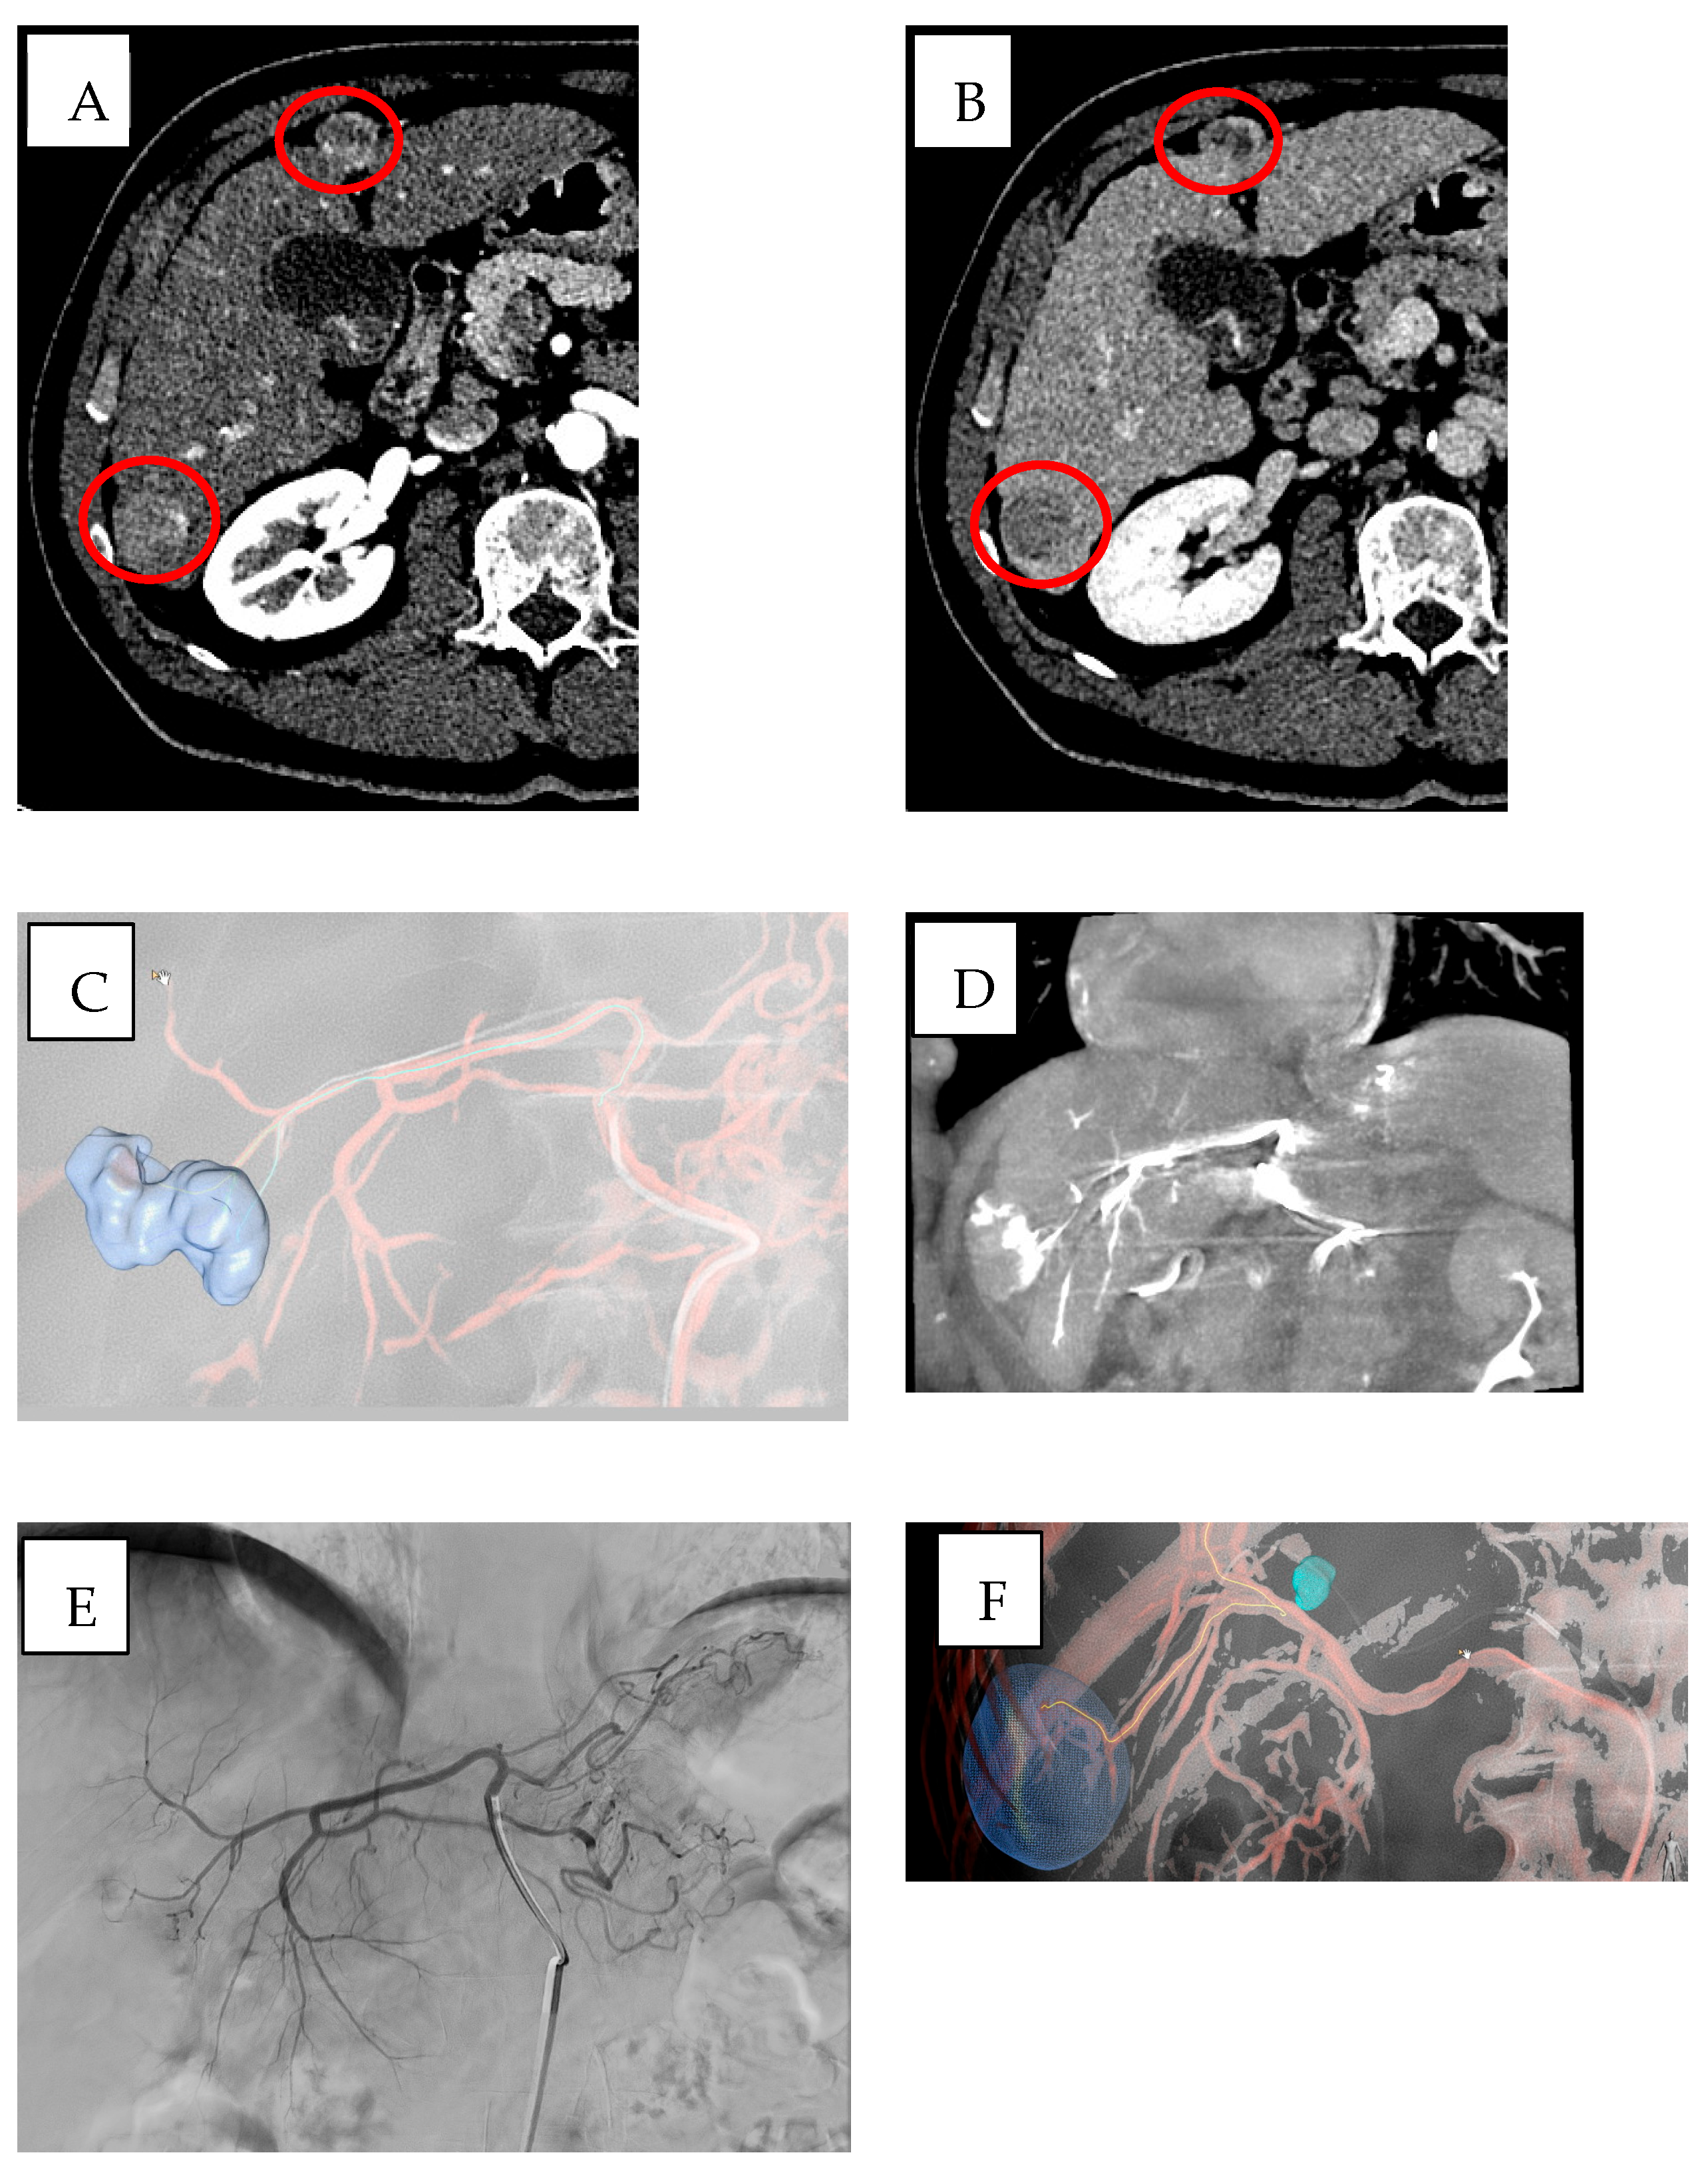

- Qin, S.; Liu, K.; Chen, Y.; Zhou, Y.; Zhao, W.; Yan, R.; Xin, P.; Zhu, Y.; Wang, H.; Lang, N. Prediction of pathological response and lymph node metastasis after neoadjuvant therapy in rectal cancer through tumor and mesorectal MRI radiomic features. Sci. Rep. 2024, 14, 21927. [Google Scholar] [CrossRef] [PubMed]

| Percutaneous applications | Barral et al. [10] | Robotic actuation and image-guided navigation | CT, MRI, US | Biopsy, prostate | Improves targeting and procedural accuracy. | |